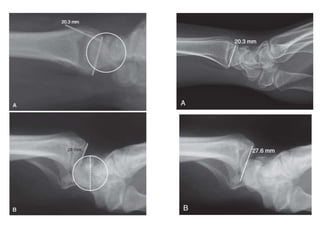

Osteotomía en consolidación viciosa

• J Am Acad Orthop Surg 2017; 25: 179-187 DOI: 10.5435 / JAAOS-D-15-00676 Derechos de autor de 2017 por la Academia Americana de

Cirujanos Ortopédicos.

• 2017 marzo, Vol 25, No 3

• Representan hasta el 18% de todas las fracturas en la población

anciana.

• Importante preguntar acerca de las secuelas de un trauma anterior

,osteoartritis existente que puede limitar el paciente

• Rx AP, lateral y oblicua

• La recomendación relativa a placa volar bloqueada frente clavos

percutáneos también se clasificó “ poco concluyente.}

Complicaciones • Mal-union yNo-union • Mal union intraarticular • Tratar con revisión > 6 semanas • Malformación angular extraarticular • Tratar con osteotomía de cuña de apertura con ORIF (PLACA BLOQUEADA ANGULO FIJO O VARIABLE CON / SIN injerto óseo • Acortamiento radial. • Asociado con mayor pérdida de función de la muñeca y cambios degenerativos en fxs extra-articulares • Tratar con acortamiento ulnar

• 79.